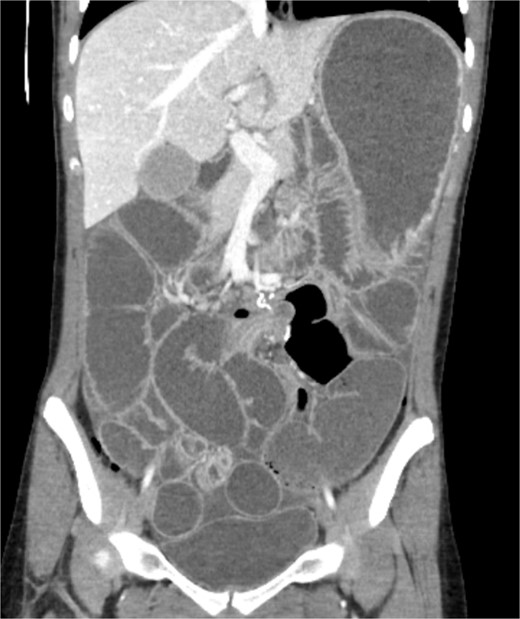

A 19-year-old female presented to the emergency department with complaints of epigastric abdominal pain, nausea, vomiting, and having passed no gas or bowel movements for 4 days. Her past medical history consisted of irritable bowel syndrome, gastroparesis, depression and anxiety, eosinophilic esophagitis, and opioid abuse. She did not take any medication for her depression and anxiety. Her past surgical history included upper and lower endoscopy and surgical ablation of genital warts. She has a significant family history of a brother who has ulcerative colitis. Upon physical exam, her abdomen was tympanic and distended. There was epigastric tenderness with no guarding or rebound tenderness. Due to concern for a bowel obstruction, a nasogastric tube was placed, and a computed tomography (CT) scan was done (Fig. 1). Imaging showed immense distension of the colon due volvulus at the splenic flexure with narrowing of the mesenteric vasculature and free fluid in the abdomen. The patient was taken for an exploratory laparotomy emergently with a preoperative diagnosis of a large bowel obstruction due to internal hernia versus volvulus. During the operation, it was found that the distal transverse colon was the point of obstruction and showed scarring with dilatation proximal to the narrowing, and there was no internal hernia identified. An extended right colectomy was performed with ileocolic anastomosis. She had a return of bowel function on postoperative Day 4. Six days post-operation, the patient began to have nausea and vomiting and had not had a bowel movement in 2 days. Eight days post-operation, a CT scan was performed that illustrated proximal small bowel dilatation (Fig. 2). With concerns of another bowel obstruction, an exploratory laparotomy was performed. During the operation, a dilated small bowel and a twisted sigmoid colon were found consistent with a large bowel obstruction secondary to sigmoid volvulus. A completion colectomy with end ileostomy was performed.

CT of the abdomen performed 8 days post operation. Shows proximal dilatation of the small bowel.